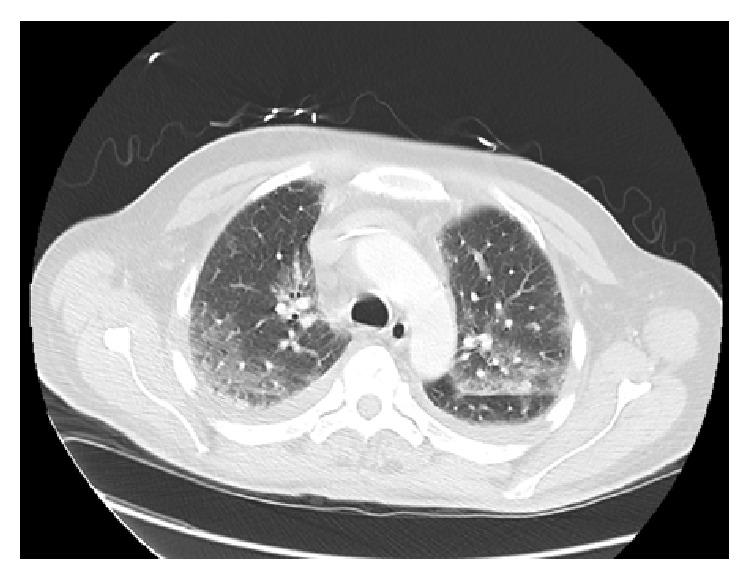

Prostate cancer is the most common cancer in men. Docetaxel is a common chemotherapeutic agent that has proven its efficacy in the treatment of patients with both castration sensitive and resistant metastatic prostate cancer. We report a case of acute respiratory distress syndrome (ARDS) in a patient with metastatic prostate cancer treated with docetaxel (Taxotere). ARDS is very rare but life threatening complication of docetaxel which requires aggressive supportive care and close monitoring. Better awareness and prompt diagnosis of this treatment related ARDS will improve the effectiveness and outcome of its management.

前列腺癌是男性中最常见的癌症。多西他赛是一种常见的化疗药物,已在去势敏感和耐药的转移性前列腺癌患者的治疗中证明了其疗效。我们报告了一例在用多西他赛(泰索帝)治疗的转移性前列腺癌患者中发生急性呼吸窘迫综合征(ARDS)的病例。ARDS是多西他赛非常罕见但危及生命的并发症,需要积极的支持治疗和密切监测。更好地认识并及时诊断这种与治疗相关的ARDS将提高其管理的有效性和结果。